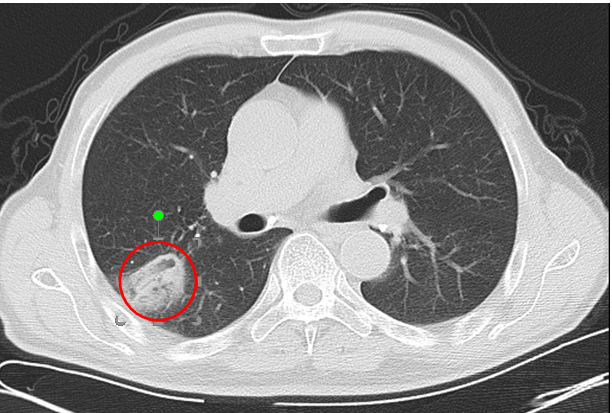

最终老唐肺结节的穿刺病理结果为肺腺癌,至今已随访4年多了,腺癌结节灭活后成了瘢痕纤维灶。

△消融后复查,箭头所指高密度为消融范围